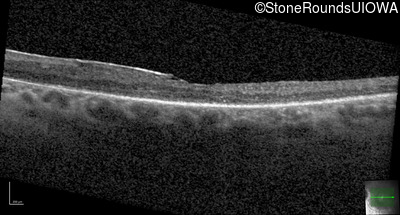

Optical Coherence Tomography - Left - 20/30 +2

Exemplar / OCT Stack

OCT Stack